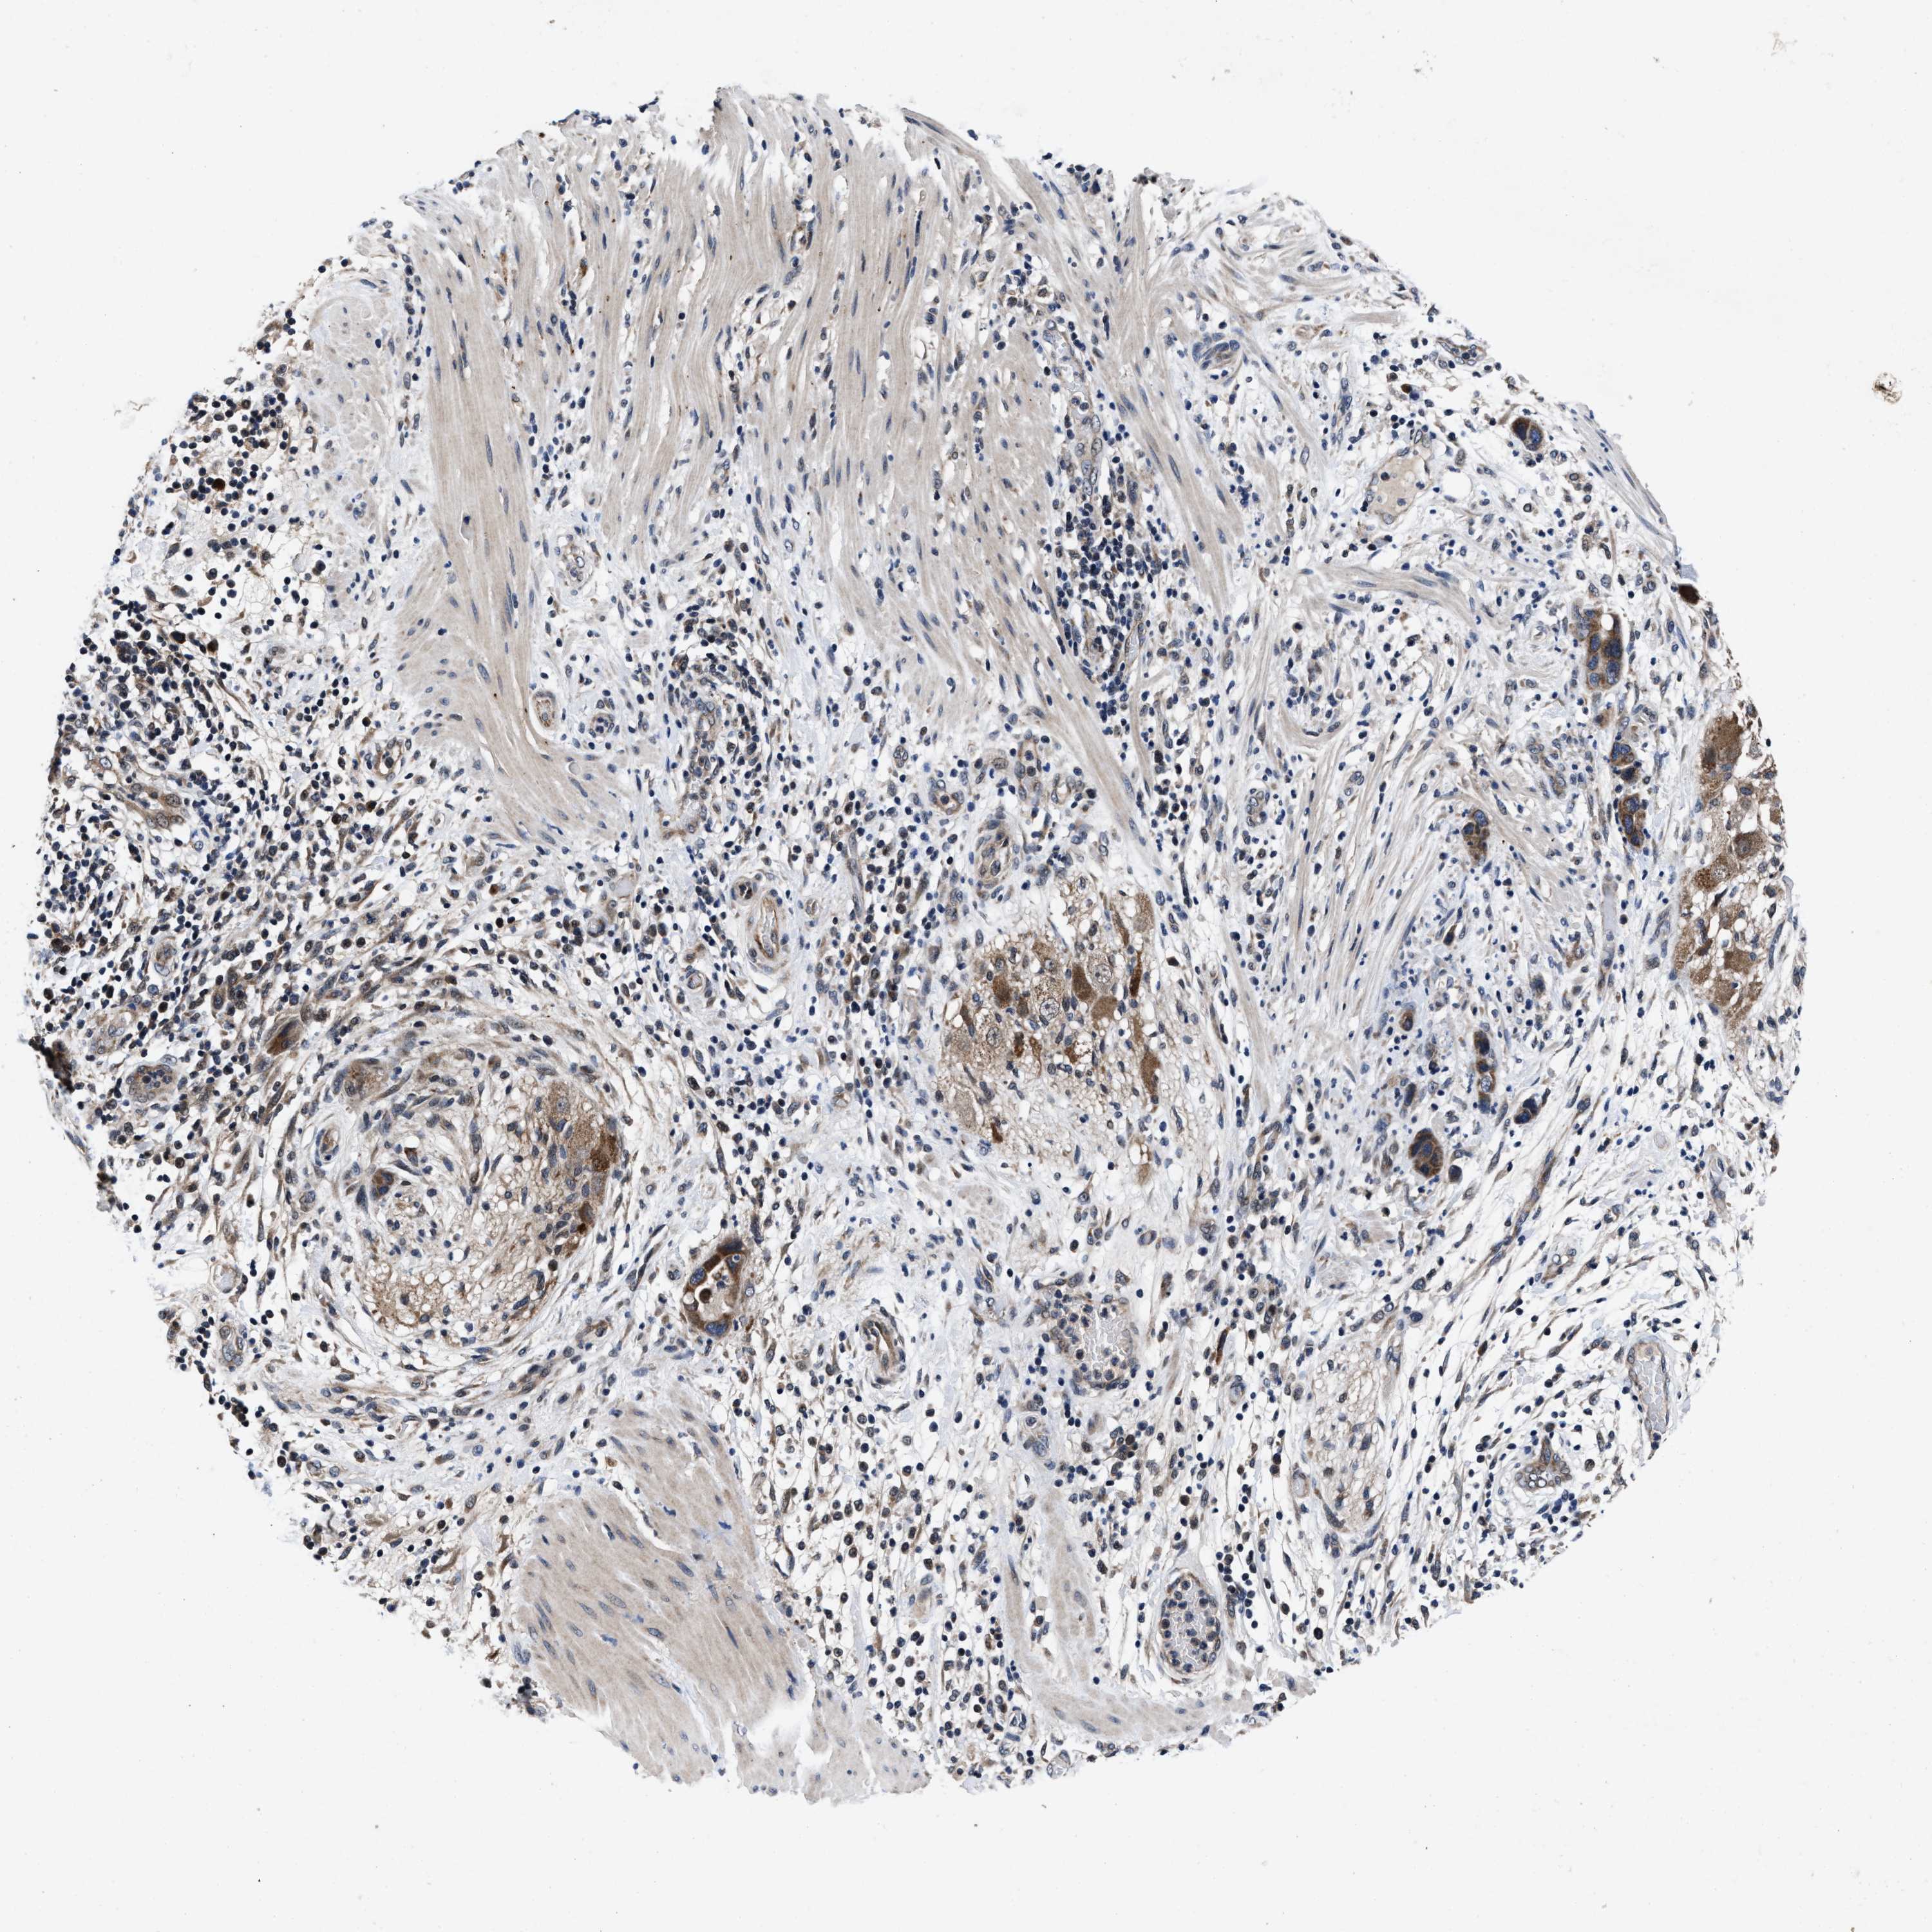

PANCREATIC CANCER - Protein expressioni

A mouse-over function shows sample information and annotation data. Click on an image to view it in a full screen mode. Samples can be filtered based on level of antibody staining by selecting one or several of the following categories: high, medium, low and not detected. The assay and annotation is described here.

Note that samples used for immunohistochemistry by the Human Protein Atlas do not correspond to samples in the TCGA dataset.

Antibody stainingi

Antibody staining in the annotated cell types in the current human tissue is reported as not detected, low, medium, or high, based on conventional immunohistochemistry profiling in selected tissues. This score is based on the combination of the staining intensity and fraction of stained cells.

Each image is clickable and will lead to virtual microscopy that enables deeper exploration of all samples and also displays staining intensity scores, fraction scores and subcellular localization as well as patient and tissue information for each sample.

Antibody HPA021134

Staining

High

Medium

Low

Not detected

Intensity

Strong

Moderate

Weak

Negative

Quantity

>75%

75%-25%

<25%

None

Location

Nuclear

Cytoplasmic/membranous

Cytoplasmic/membranous,nuclear

Adenocarcinoma, NOS